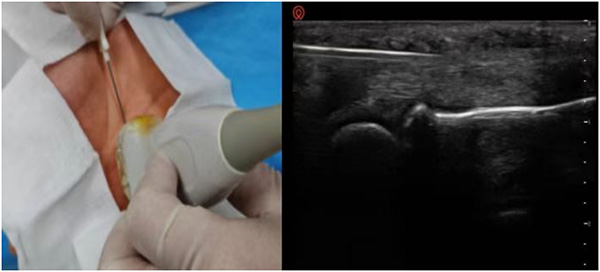

科室以超声可视化技术为核心,打造精准镇痛体系,彻底告别传统镇痛“盲探”模式。超声可清晰呈现深层解剖结构,全程实时引导穿刺操作,确保神经阻滞、针刀松解等治疗的精准度与安全性,让每一次治疗都直达病灶、有的放矢。超声引导下神经阻滞术、超声引导针刀松解术等特色技术,适配多种疼痛病症,创口微小、恢复快速、疗效确切,吸引河北、内蒙古等多地患者慕名就诊,用精准疗效赢得广泛认可。

超声可视化注射治疗技术

超声可视化神经阻滞治疗技术

超声可视化针刀技术技术